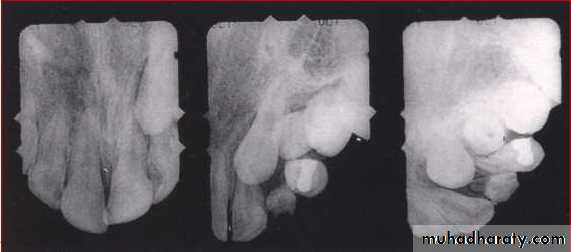

Periapical

Mandibular archOPG

Lateral ceph

Extraoral

RADIOGRAPHS

I. Qualitative radiographs

Maxillary archOcclusal

PAview

Max. ant. occlusal

Parallax method

OPG

Panoramic radiographs are basic radiograph

for assessment of impacted teeth•

•

Tooth position whether deep or shallow

General orientation horizontal or inclined

mesially/distallyRelationship with neighbouring teeth

Risk of their transpositionPresence or absence of apical resorption of

roots of adjacent teeth